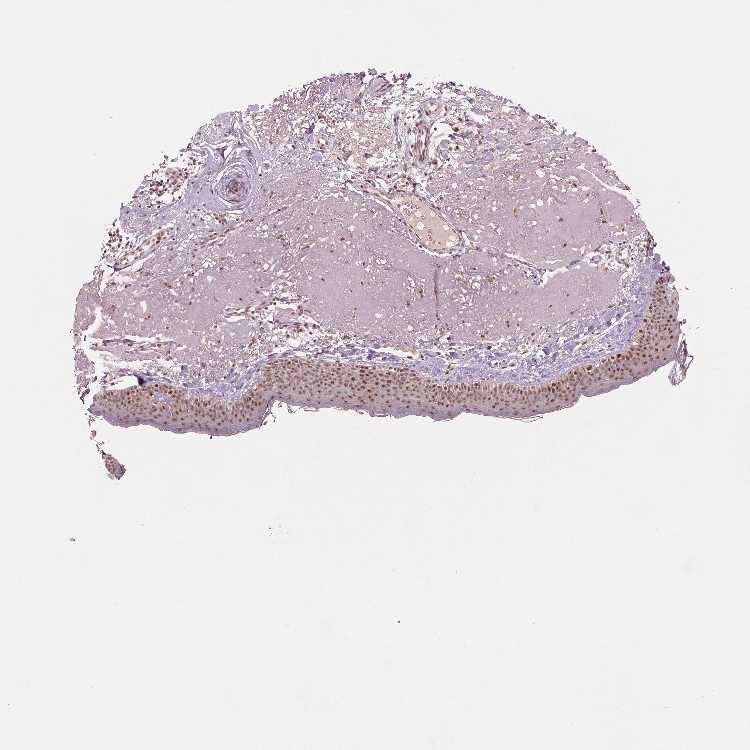

SKIN 1 - Antibody stainingi

Antibody staining in the annotated cell types in the current human tissue is reported as not detected, low, medium, or high, based on conventional immunohistochemistry profiling in selected tissues. This score is based on the combination of the staining intensity and fraction of stained cells.

Each image is clickable and will lead to virtual microscopy that enables deeper exploration of all samples and also displays staining intensity scores, fraction scores and subcellular localization as well as patient and tissue information for each sample.

Antibody HPA066832

Langerhans Medium

Fibroblasts Medium

Keratinocytes Medium

Melanocytes Medium